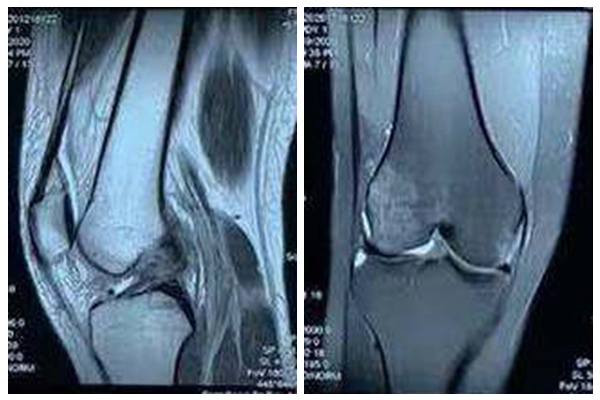

患者蘆女士,安徽財(cái)經(jīng)大學(xué)一名大一的學(xué)生,酷愛運(yùn)動(dòng)。2020年11月15日蘆女士在一場(chǎng)籃球比賽中不慎扭傷右膝關(guān)節(jié),隨即出現(xiàn)右膝關(guān)節(jié)腫痛、無法行走,后輾轉(zhuǎn)至多家醫(yī)院就診,迫切希望能快速恢復(fù)膝關(guān)節(jié)功能,重返運(yùn)動(dòng)。經(jīng)多方咨詢,前來蚌埠醫(yī)學(xué)院第一附屬醫(yī)院骨科就診。李寬新接診后第一時(shí)間詳細(xì)詢問病史、體格檢查,結(jié)合患者術(shù)前影像學(xué)檢查,診斷為:“右膝關(guān)節(jié)前交叉韌帶斷裂”。給患者提出“應(yīng)用自體Hamstring肌腱關(guān)節(jié)鏡下實(shí)施前交叉韌帶個(gè)性化解剖重建”的治療方案。

李寬新主任、張衡博士進(jìn)行了詳細(xì)的術(shù)前設(shè)計(jì),在膝關(guān)節(jié)磁共振上測(cè)量前交叉韌帶脛骨止點(diǎn)大小,在B超上評(píng)估半腱肌腱、股薄肌腱的粗細(xì),確定股骨、脛骨隧道的最佳解剖位置。2020年12月22日李寬新主任、張衡博士共同為患者實(shí)施關(guān)節(jié)鏡下自體Hamstring肌腱前交叉韌帶個(gè)性化解剖重建手術(shù)。術(shù)中應(yīng)用自主研發(fā)的關(guān)節(jié)鏡下測(cè)量器測(cè)量前交叉韌帶脛骨止點(diǎn)面積,按照張衡博士改良的韌帶大小計(jì)算公式計(jì)算出需要移植的Hamstring肌腱的直徑,并采用國(guó)際流行的Three portal 和AAMP法建立股骨隧道技術(shù)實(shí)施肌腱移植。手術(shù)僅4個(gè)Mini小切口,微創(chuàng)、美觀。術(shù)后膝關(guān)節(jié)X線示:前交叉韌帶隧道方向、膝關(guān)節(jié)解剖關(guān)系良好。